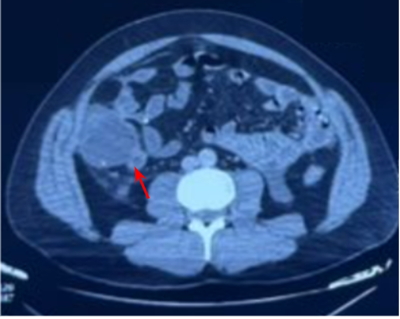

After 48 hours, the patient showed clinical and biological deterioration: ongoing abdominal pain, persistent cloudy effluent, and development of bowel obstruction symptoms (absence of stool and gas). An abdominal X-ray showed diffuse colonic gas without air-fluid levels. An abdominal CT scan revealed acute latero-cecal appendicitis, characterized by cecal fluid distension extending to the ascending colon (measuring 56 mm), with the PD catheter still in place in the pelvis (Figure 1:).

Figure 1:CT scan image confirming the diagnosis of acute appendicitis (red arrow)